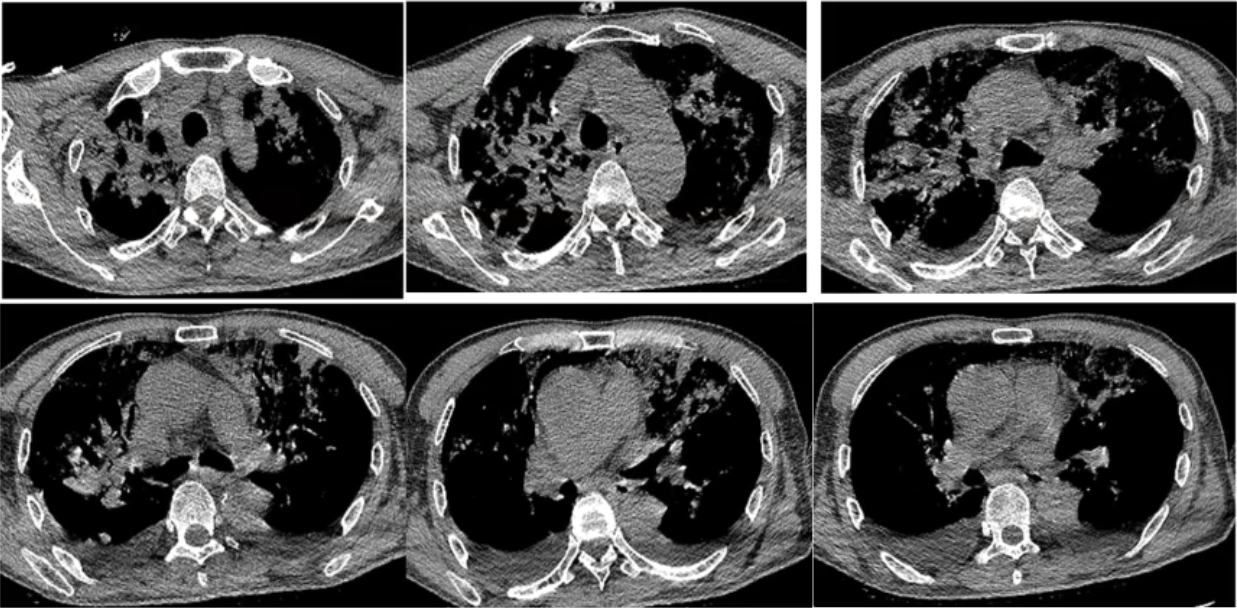

复查胸部CT(2020-12-16):双上肺病变仍然较重,双下肺重力依赖区实变影明显吸收,双侧少量胸腔积液(图5)。

图5 患者胸部CT(2020-12-16)